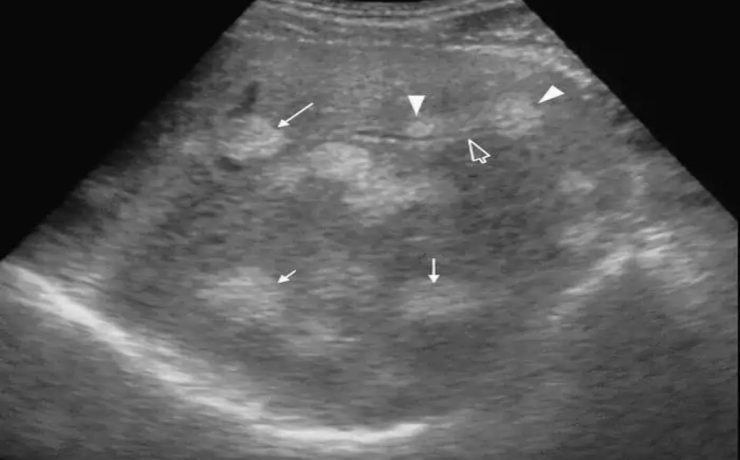

El cólico nefrítico se define como un dolor agudo en el flanco (en ocasiones se irradia a la ingle) escrito por los pacientes como el peor de su vida y que generalmente se acompaña de náuseas, vómitos y hematuria. La litiasis es un agregado policristalino compuesto de cristaloides (95%) y